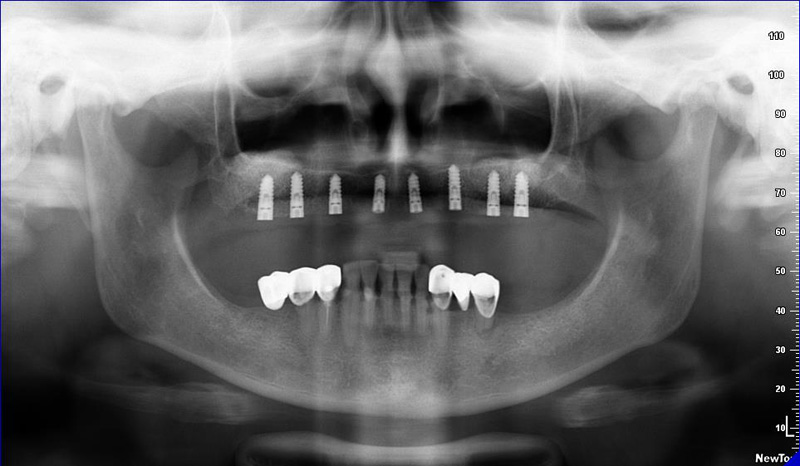

Lékař si vytvoří všechny typy zobrazení potřebných pro naplánování – tedy 2D snímky (panoramatický), příčné řezy i 3D model.

Vidí zde i důležité anatomické útvary – čelistní dutinu, průběh nervu atd. Po proměření množství kosti – šířky i výšky vybere z databáze vhodný typ implantátu a umístí ho do požadované lokality.

Ihned vidí jeho pozici ve všech 3 rovinách a na všech snímcích i 3D modelu. Může upravovat podle potřeby jeho pozici, sklon atd.

Všechny vybrané a správně umístěné simulované implantáty se ukládají do „počítačové karty“ pacienta s jejich pozicí, délkou, průměrem, typem i sklonem.

Lékař i pacient tedy ještě před vlastní operací vidí, jak by mělo ošetření probíhat a vypadat.